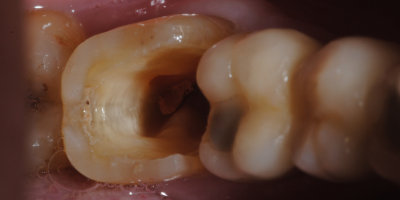

Indirect restorations are indicated for posterior teeth (premolars and molars) when the teeth have large cavities (usually resulting from caries) or simply to replace old restorations.

• Root canal teeth that have undergone significant crown wear, with their rigidity and strength drastically reduced. Indirect restorations restore the tooth’s rigidity and strength, protecting it and preventing the common fractures characteristic of root canal teeth.

• Posterior teeth with fractures that compromise the structural solidity of the crown, where an indirect partial coverage restoration is indicated;